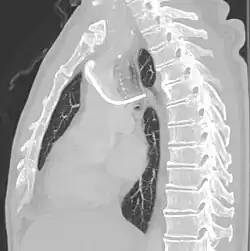

A port consists of a reservoir compartment (the portal) that has a silicone bubble for needle insertion (the septum), with an attached plastic tube (the catheter). The device is surgically inserted under the skin in the upper chest or in the arm and appears as a bump under the skin. It requires no special maintenance other than occasional flushing to keep clear. It is completely internal so swimming and bathing are not a problem. The catheter runs from the portal and is surgically inserted into a vein (usually the jugular vein or less optimally the subclavian vein). Ideally, the catheter terminates in the superior vena cava or the right atrium. This position allows infused agents to be spread throughout the body quickly and efficiently.

The port is then sutured on two sites to the underlying muscles. The tip of the catheter is checked for kinks and position using a fluoroscope. Besides that, aspiration of blood and contrast injection through the chemoport can also be used to confirm the position. The port is the closed in two layers (subcutaneous tissue is sutured first, followed by the skin). Sterile dressing is then placed on the port.[3] The optimum site to park the tip of the catheter is at the cavo-atrial junction or with margin of error of not more than 4 cm above the junction.[3]

Ports can be put in the upper chest or arm. The exact positioning itself is variable as it can be inserted to avoid visibility when wearing low cut shirts, and to avoid excess contact due to a backpack or bra strap. The most common placement is on the upper right portion of the chest, with the catheter itself looping through the right jugular vein, and down towards the patient's heart.

The incidence of catheter fracture is 2.3%. The fracture can be due to "pinch-off syndrome" when the vein and the catheter is compressed when passes between the clavicle and first rib before turning 90 degrees into the superior vena cava. Fractured catheter component can dislodge most commonly into pulmonary arteries (35%), right atrium (27%), right ventricle (22%), and superior vena cava and peripheral veins (15.4%).[5]